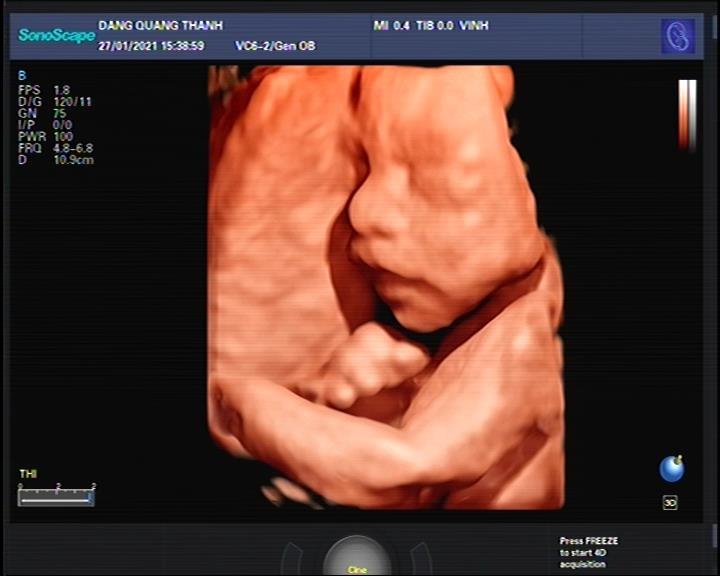

- Máy siêu âm 5D SonoScape P25 với S-live real time: bác sĩ vừa khám, vừa sử dụng chế độ S-live làm mịn và nét hình ảnh, không cần dừng lại để sử dụng như trước.

- Chế độ auto-face: tự động bắt hình ảnh khuân mặt em bé

Hình ảnh thực tế trên máy siêu âm 5D SonoScape P25